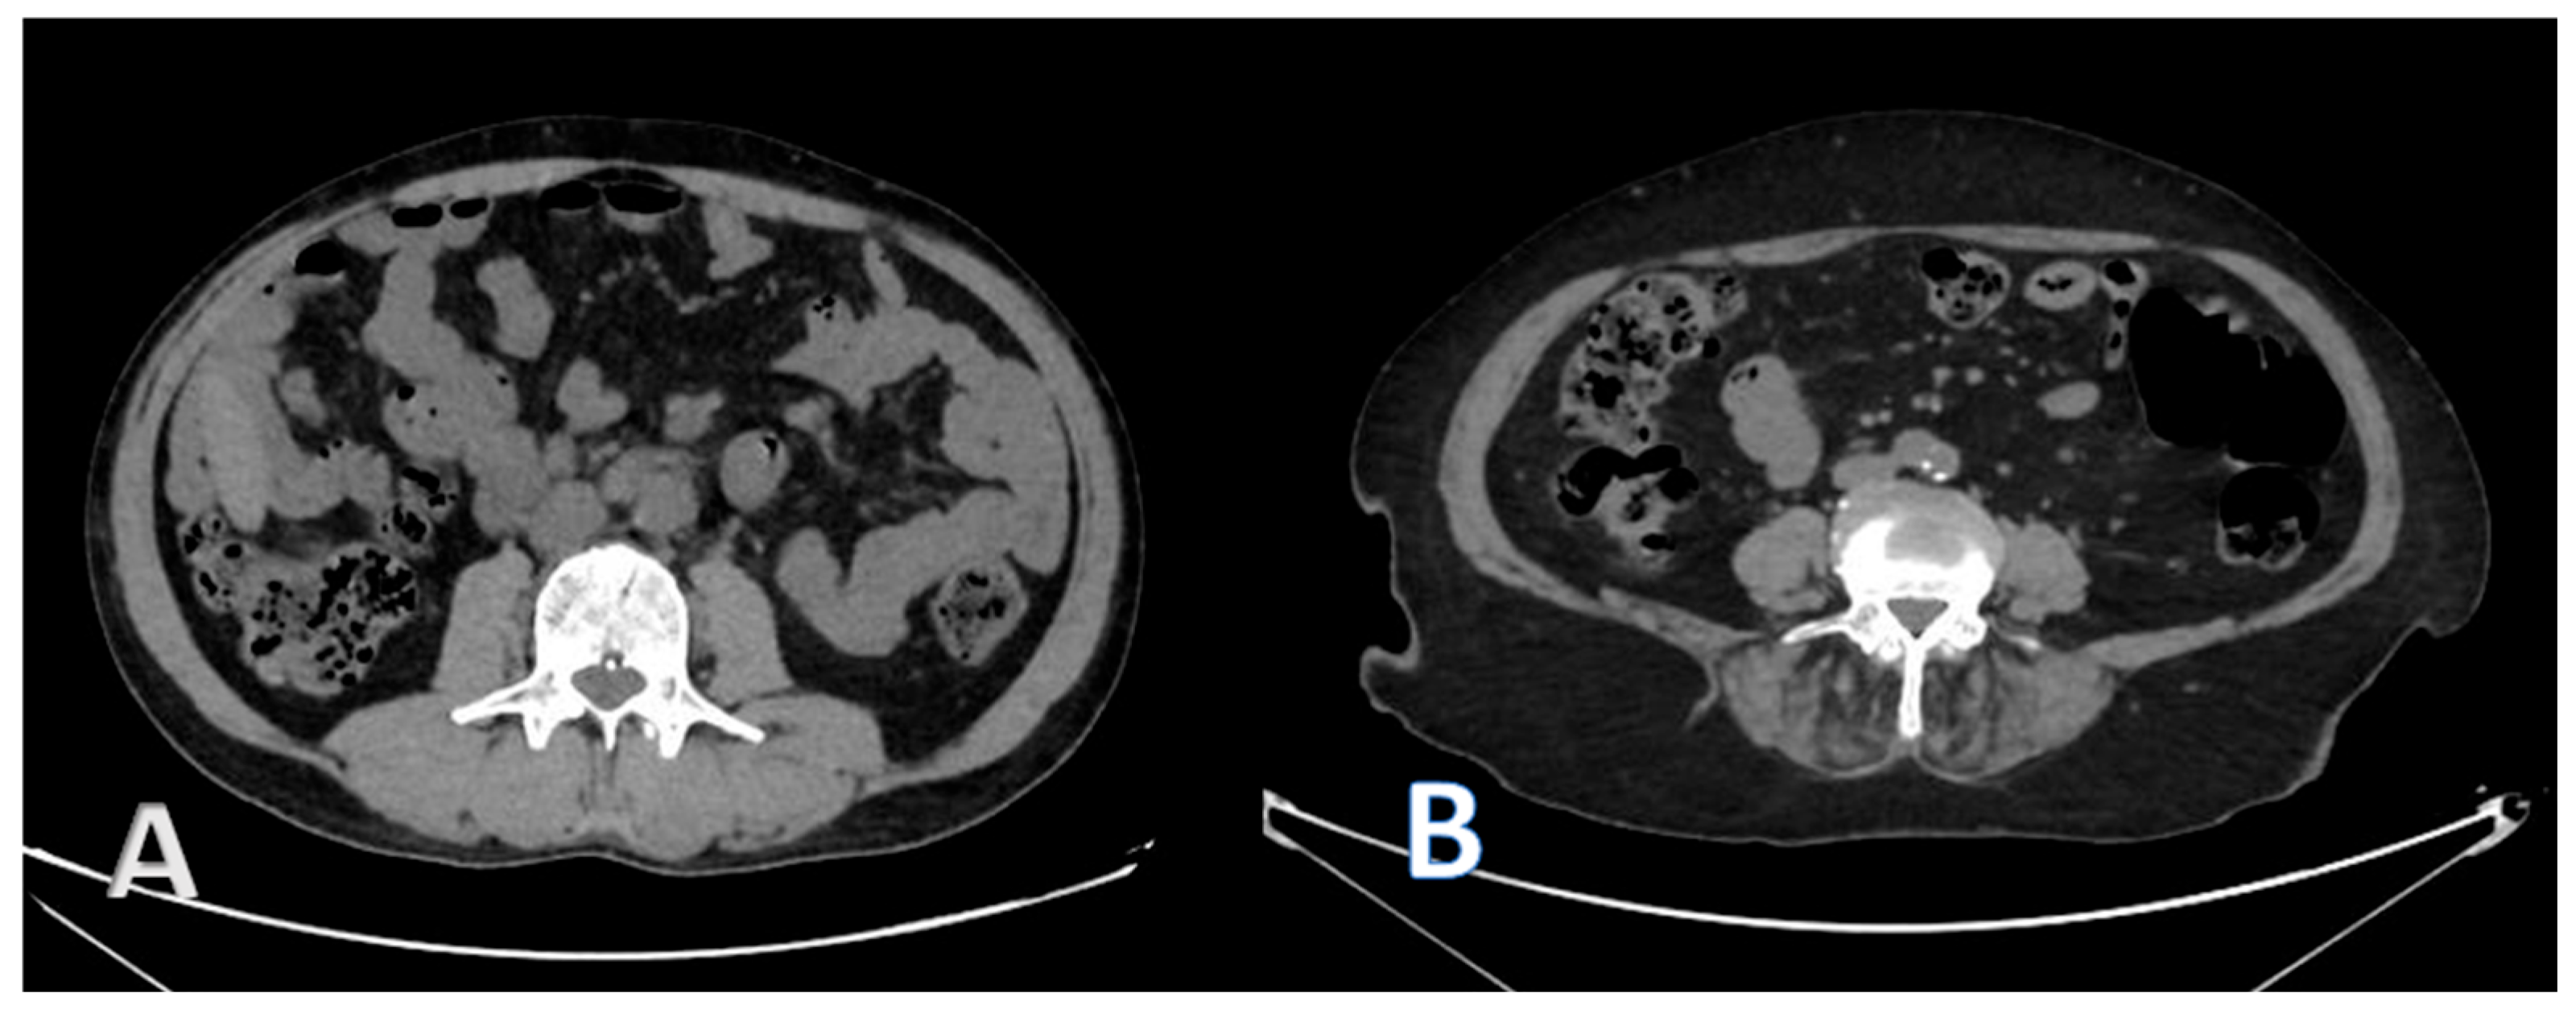

2.3. CT Image Acquisition and Analysis

2.4. Body Composition Parameters